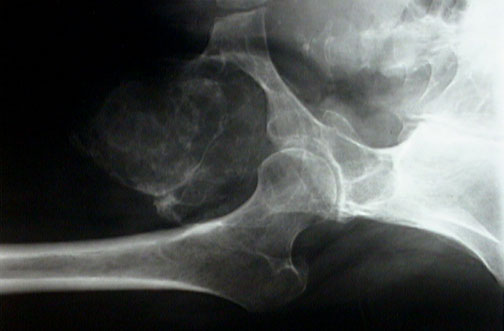

Click on the giant cell tumor in the radiograph above:

This is a radiograph of a giant cell tumor involving the left ischial ramus. The tumor is an eccentric, expansile, lytic mass with extension into soft tissue along with overlying reactive new bone formation.